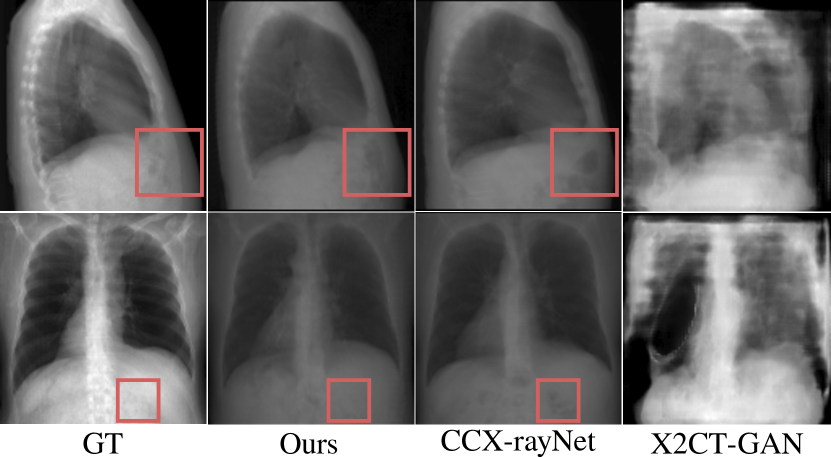

Refer to caption

Figure 9: Examples of the correlated 3D projections from our proposed approach compared to alternative supervised methods X2CT-GAN [49] and CCX-rayNet [35].

In Table 2 we compare our approach to paired alternative methods in terms of quality of the 3D outputs for both in- and out-of-distribution inputs. Despite variations in datasets originating from different imaging systems, resolutions, and patients’ health conditions, our model demonstrates superior performance across all metrics and maintains consistency across all out-of-distribution datasets. Refer to Figures 5 and 9 for qualitative results.